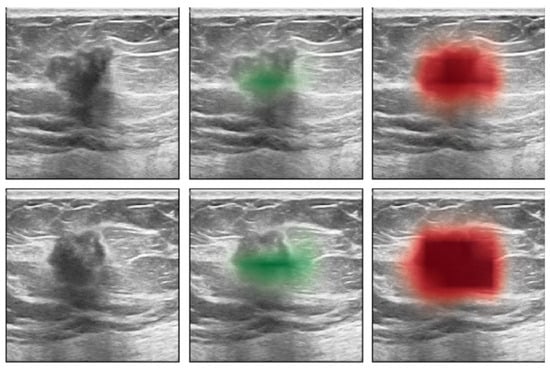

9. Molecular Breast Imaging (MBI)

- Shen, Y.; Shamout, F.E.; Oliver, J.R.; Witowski, J.; Kannan, K.; Park, J.; Wu, N.; Huddleston, C.; Wolfson, S.; Millet, A.; et al. Artificial intelligence system reduces false-positive findings in the interpretation of breast ultrasound exams. Nat. Commun. 2021, 12, 5645. [Google Scholar] [CrossRef]

- Mango, V.L.; Sun, M.; Wynn, R.T.; Ha, R. Should we ignore, follow, or biopsy? Impact of artificial intelligence decision support on breast ultrasound lesion assessment. Am. J. Roentgenol. 2020, 214, 1445–1452. [Google Scholar] [CrossRef]